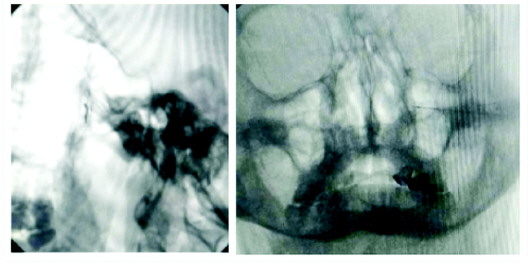

治疗经过:为该患者行经翼颚窝蝶颚神经节射频治疗。患者取仰卧位,穿刺点定点位于鼻翼旁与眶外缘连线交点,常规消毒铺巾,10cm射频穿刺针穿刺,在C臂下调整进针方向,C臂透视下正位针尖位于圆孔下方,中鼻甲外侧,侧位位于翼腭窝中上三分之一。穿刺针针芯拔出,植入射频电极,测试阻抗为216欧姆,高频测试诱发复制症状良好,行蝶腭神经节脉冲射频调节,术后疼痛消失。随访患者至今,疼痛未复发。